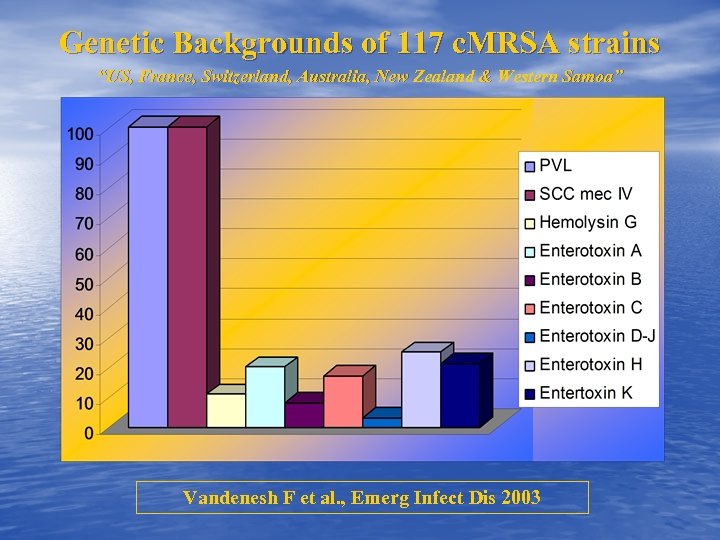

Genetic Backgrounds of 117 c. MRSA strains “US, France, Switzerland, Australia, New Zealand & Western Samoa” Vandenesh F et al. , Emerg Infect Dis 2003

Genetic Backgrounds of 117 c. MRSA strains “US, France, Switzerland, Australia, New Zealand & Western Samoa” Vandenesh F et al. , Emerg Infect Dis 2003